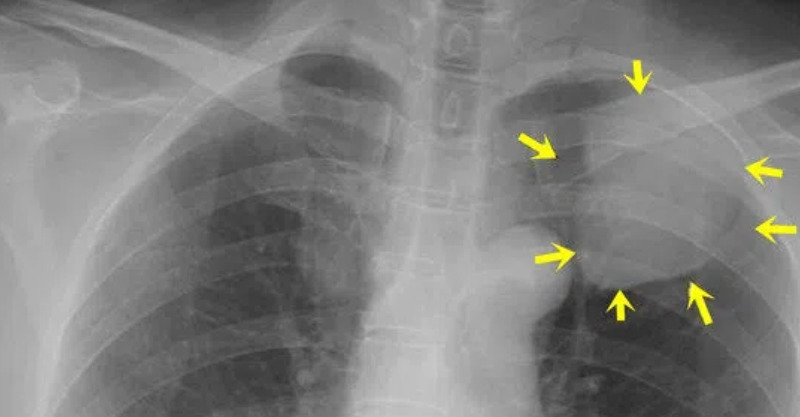

隨著觀念的更新和科普知識的普及,大家越來越重視癌症的早診檢查:或主動去檢查,或因為其他疾病而拍胸片或做胸部CT ,偶然發現肺部了結節,這種情況越來越多見。很多人很擔心,這肺長了結節,會不會是得了肺癌?接下來該怎麼辦?這確實是個問題。